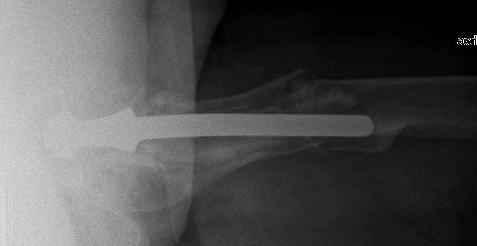

Спасибо за обсуждение. После нескольких дней тракции аппаратом сделали. Попытка закрытой репозиции не удалась из-за смещения по ширине, мешали фрагменты цемента. После их удаления репозиция получилась. Еще убрали немного цемента с ножки по латерльной стороне, чтобы обнажить 40-50 мм ее дистальной части, для плотной посадки гвоздя. Дальнейшее введение гвоздя было несложным. Протез показался нам стабильным в проксимальной части как латерально, так и медиально. Картинки в приложении.

THX for the discussion. After few days of traction by ex-fix the surgery was performed. An attempt of closed nailing was unsuccesful because of fragment translation, which was blocked by cement fragments. After removal of broken cement pieces reduction was reached "automagically". Also some cement from lateral part was removed by

chisel to expose distal 40-50 mm of the stem to allow tight fit of the nail. Further fixation by the nail was pretty easy and straightforward. Images attached. The stem looked stable in its proximal part both laterally and medially. Comments/critics are welcome.

The nail tip is jammed. Since it is conical, it can only be jammed more with axial load.